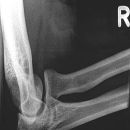

Ellenbogen ventro-dorsal (1. Ebene a.-p.)

Abbildungskriterien

distale Humerunsanteile: Epikondylen, Capitulum humeri

proximale Unterarmanteile: Radius-Radiusköpfchen und -hals, Ulna -Schaft, Körper, Olecranon

Qualitätskriterien

Ellenbogengelenk vollständig a.p. orthograd abgebildet, Gelenkspalt in Filmmitte und überlagerungsfrei.